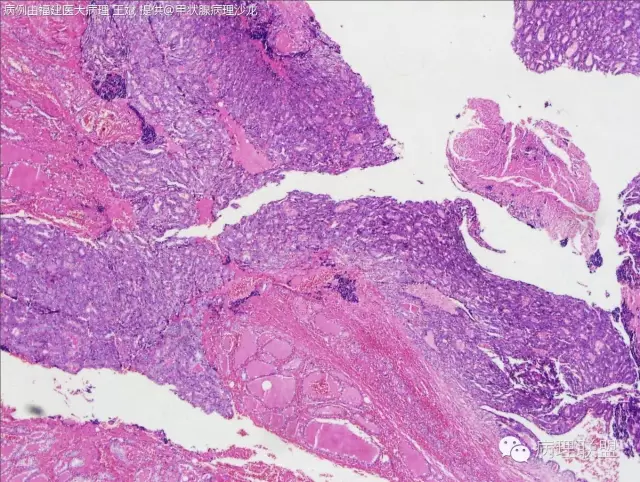

女性,20岁,甲状腺肿物(本病例由福建医大病理 王斌提供,致谢!)

Encapsulated follicular variant papillary thyroid carcinoma with capsular invasion——如总体为包裹性滤泡性病变的话(图一提示,但只一部分)

@济宁医学院附属医院 张仁亚 @山东大学齐鲁医院 病理 刘志艳 只此一灶,组织切切破了

我担心的包膜侵犯是不是切破了造成的假象,我补一个MASSON染色看看

不太像假象

@福建医大病理 王斌 ,我觉得不是切破,上方也有浸润的趋势。